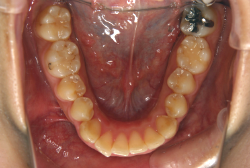

叢生(そうせい)

凸凹な歯並びのことを叢生といいます。矯正歯科に来院する患者様の主訴の中で、最も多いのが「配列の凸凹を真っ直ぐにしたい」というものです。歯の大きさと顎の大きさの調和がとれていないことが原因です。

凸凹を主体としたケースの場合、当院の平均治療期間は18ヶ月ですので、このケースは少し長めに経過しました。理由の一つは凸凹の程度がかなり重症だったと言うことですが、もう一つは、右下第2大臼歯が45度くらい前傾していたため、それを整直化させるために時間を要したと考えています。いずれにしても最終結果は大変よい状態と思います。

治療前は並びが乱れて見た目が悪いというのはもちろん問題ですが、歯科医学的に一番困るのは噛み合わせが悪いという点です。上下の犬歯(3番目の歯)は、上下的に離れた位置にあるため接触することができません。つまり歯としては存在していても、歯としては機能していないということです。